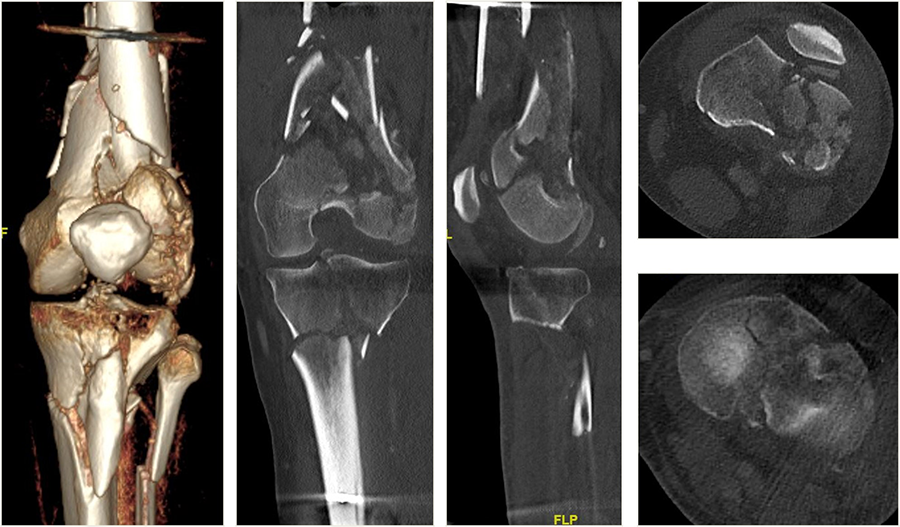

A 64-year-old man was involved in a car injury and sustained a complex floating knee injury with a comminuted distal femoral fracture and a proximal tibial fracture on the left side among various other fractures (Fig 5).